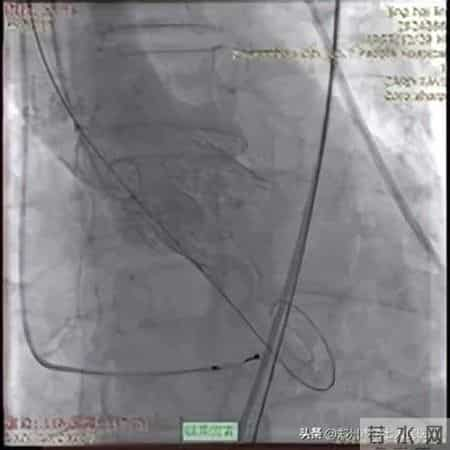

在充分的术前准备之后,手术的大幕正式拉开。在手术过程中,张申伟教授精准操作J-VALVE TF系统,通过股动脉路径微小切口,在“自主导航定位系统”引导下,将人工瓣膜准确输送至病变部位。在释放瓣膜的关键环节,他凭借对系统性能的深刻理解和娴熟的操作手法,精确调整瓣膜位置和角度,确保瓣膜与自体瓣环完美贴合。整个手术过程紧张有序,最终成功完成瓣膜置换。术后,患者心脏功能得到明显改善,第二天即下床活动,最终顺利康复出院。